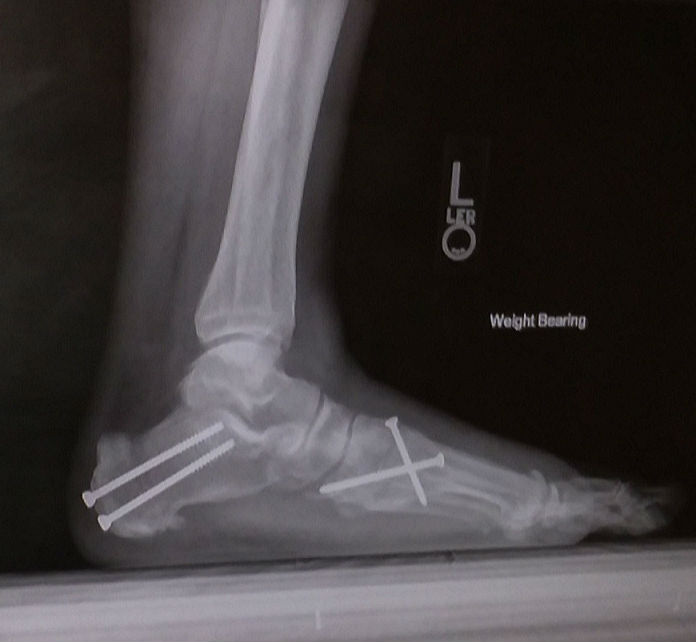

Seven years ago while commuting to home on the subway after work, I felt a twinge in my foot as I was standing on the train. The next day, I couldn't get out of bed due to the pain. Subsequent evaluations revealed a torn post tibial tendon by several orthopedic surgeons. The protocol described to me was both harrowing and would require extensive recuperation and time off from work, so I delayed the procedure until I was retired and had the free time to recuperate. So, for 7 years I hobbled around with a limp and constant pain when I walked. I had the surgery performed at the beginning of July 2018 and it involved a complete flat foot reconstruction requiring tendon replacement and hamstring modification. I was not able to go full weightbearing for several months. Only in the November/December timeframe did I consider myself fully ambulatory. I am now scheduled for my final post-op visit in June 2019. I am extremely satisfied with the outcome and cannot complement HSS staff enough for their professionalism and expertise. Kudos to Dr. D. et. al.